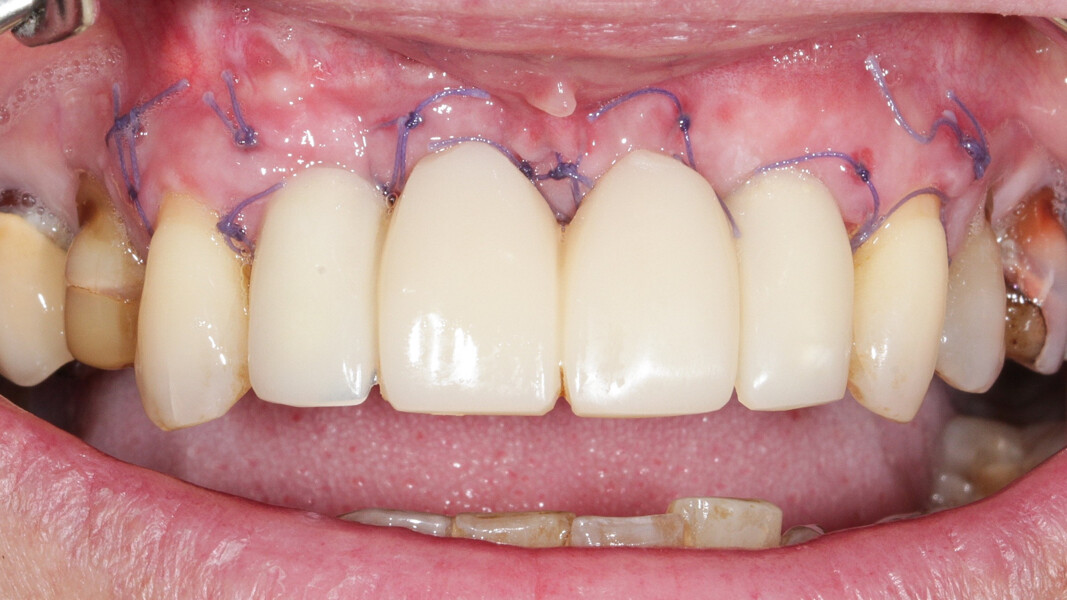

Nous réalisons un lambeau avec une incision crestale décalée en palatin en 11 et 21, sulculaire en 12, 13, 22, 23, en prenant soin de préserver les papilles interdentaires, ainsi que deux décharges verticales en distal des canines. Nous réalisons un décollement de pleine épaisseur (Figs. 28 et 29). Les dents (12, 22 et 18) sont facilement extraites et les alvéoles curetées avec soins. Deux implants (4*13) sont positionnés dans la paroi palatine des alvéoles, il subsiste une déhiscence vestibulaire en 22. Les racines de 12, 22 et 18 sont séparées dans le sens de la longueur. Les racines préparées comme indiqué ci-dessus, sont vissées en vestibulaire et en occlusal de la crête, au moyen de vis d’ostéosynthèse (diamètre 0,9 mm), afin de reconstruire la crête osseuse au niveau des inters de bridge ainsi que la paroi vestibulaire de la crête au niveau de 22 (Figs. 30 et 31). Le gap vestibulaire entre les implants et la crête ainsi que l’espace entre la crête et le greffon au niveau de 21, sont comblés avec un matériau d’origine synthétique (Collapat II Symatese). Le lambeau est tracté, suturé coronairement avec un fil tressé synthétique 5.0 (Fig. 32). Des piliers coniques droits pour prothèse plurale transvissée sont posés, et une empreinte prise à la fin de l’intervention (Fig. 33). Un provisoire est réalisé dans la journée par notre laboratoire de prothèse et posé le soir même. (Figs. 34 et 35)

Les sutures sont retirées à 15 jours. Un contrôle de la bonne ostéointégration des implants est réalisé à 2 mois postopératoire (Figs. 36 et 37). La réalisation de la prothèse d’usage par notre correspondant intervient à 9 mois postopératoire (Fig. 38).